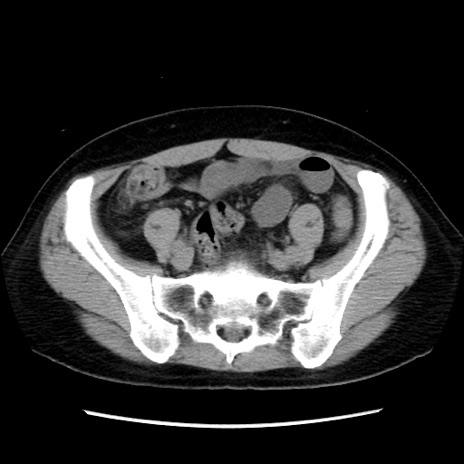

症例10(横断像)

【症例】 50歳代女性

【主訴】 腹痛

【現病歴】前日生レバーを食べた。今朝に排便あり。 昼前に突然発症の腹痛を生じ、当院救急外来を受診した。

【既往歴】 子宮筋腫にてで子宮全摘後

【身体所見】 意識清明、腹部:平坦、軟、下腹部やや左を中心に圧痛・反跳痛あり、筋性防御あり

【データ】WBC 7800、CRP 0.07